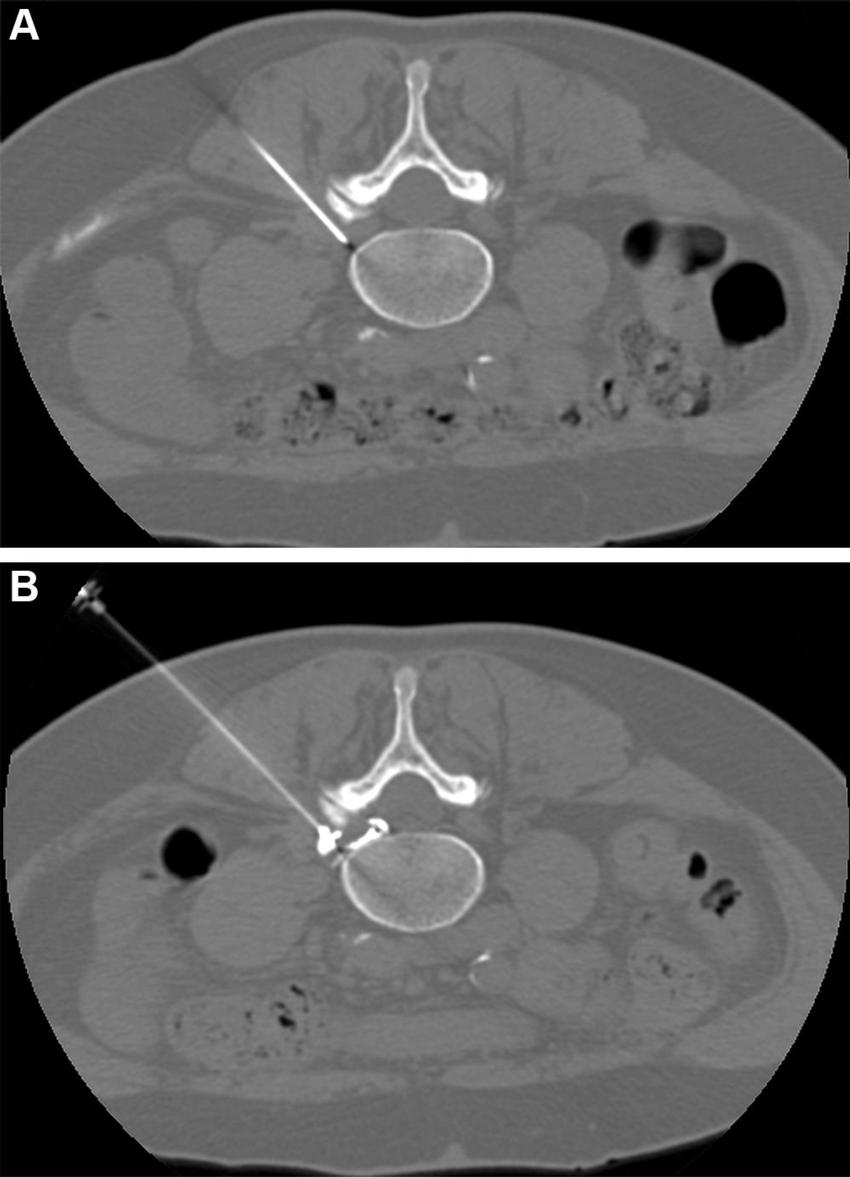

Figure 2. CT-guided pulsed radiofrequency (PRF) with transforaminal epidural steroid injection. A 62-year-old woman underwent PRF followed by transforaminal epidural steroid injection for sciatica due to left contained intraforaminal disk herniation at the L4-5 level. (A) A 22-gauge needle electrode with a 10-mm active tip was introduced and advanced using one 3-mm oblique axial unenhanced CT scan, which revealed that the needle tip was proximate to the target dorsal root ganglion with the lateral foraminal portal of entry. (B) Sensitive stimulation (50 Hz) PRF current with a threshold of no more than 0.2 V was used to confirm proper positioning by evoking tingling or electric pain in the dermatome that had to match the target dorsal root ganglion. Therapeutic PRF was then performed in one 10-minute session with E-dose functionality, maintaining temperature below the threshold for neural damage (42°C) and a constant voltage (45 V). Immediately after PRF administration, epidural spread of 0.3 mL of contrast material was confirmed using intermittent intraprocedural CT fluoroscopic imaging with no intravascular contrast material flow demonstration. A combination of steroid and anesthetic (1 mL lidocaine [ 20 mg/mL] and 2 mL dexamethasone [10 mg/mL]) was then injected without altering needle position to conclude the procedure.